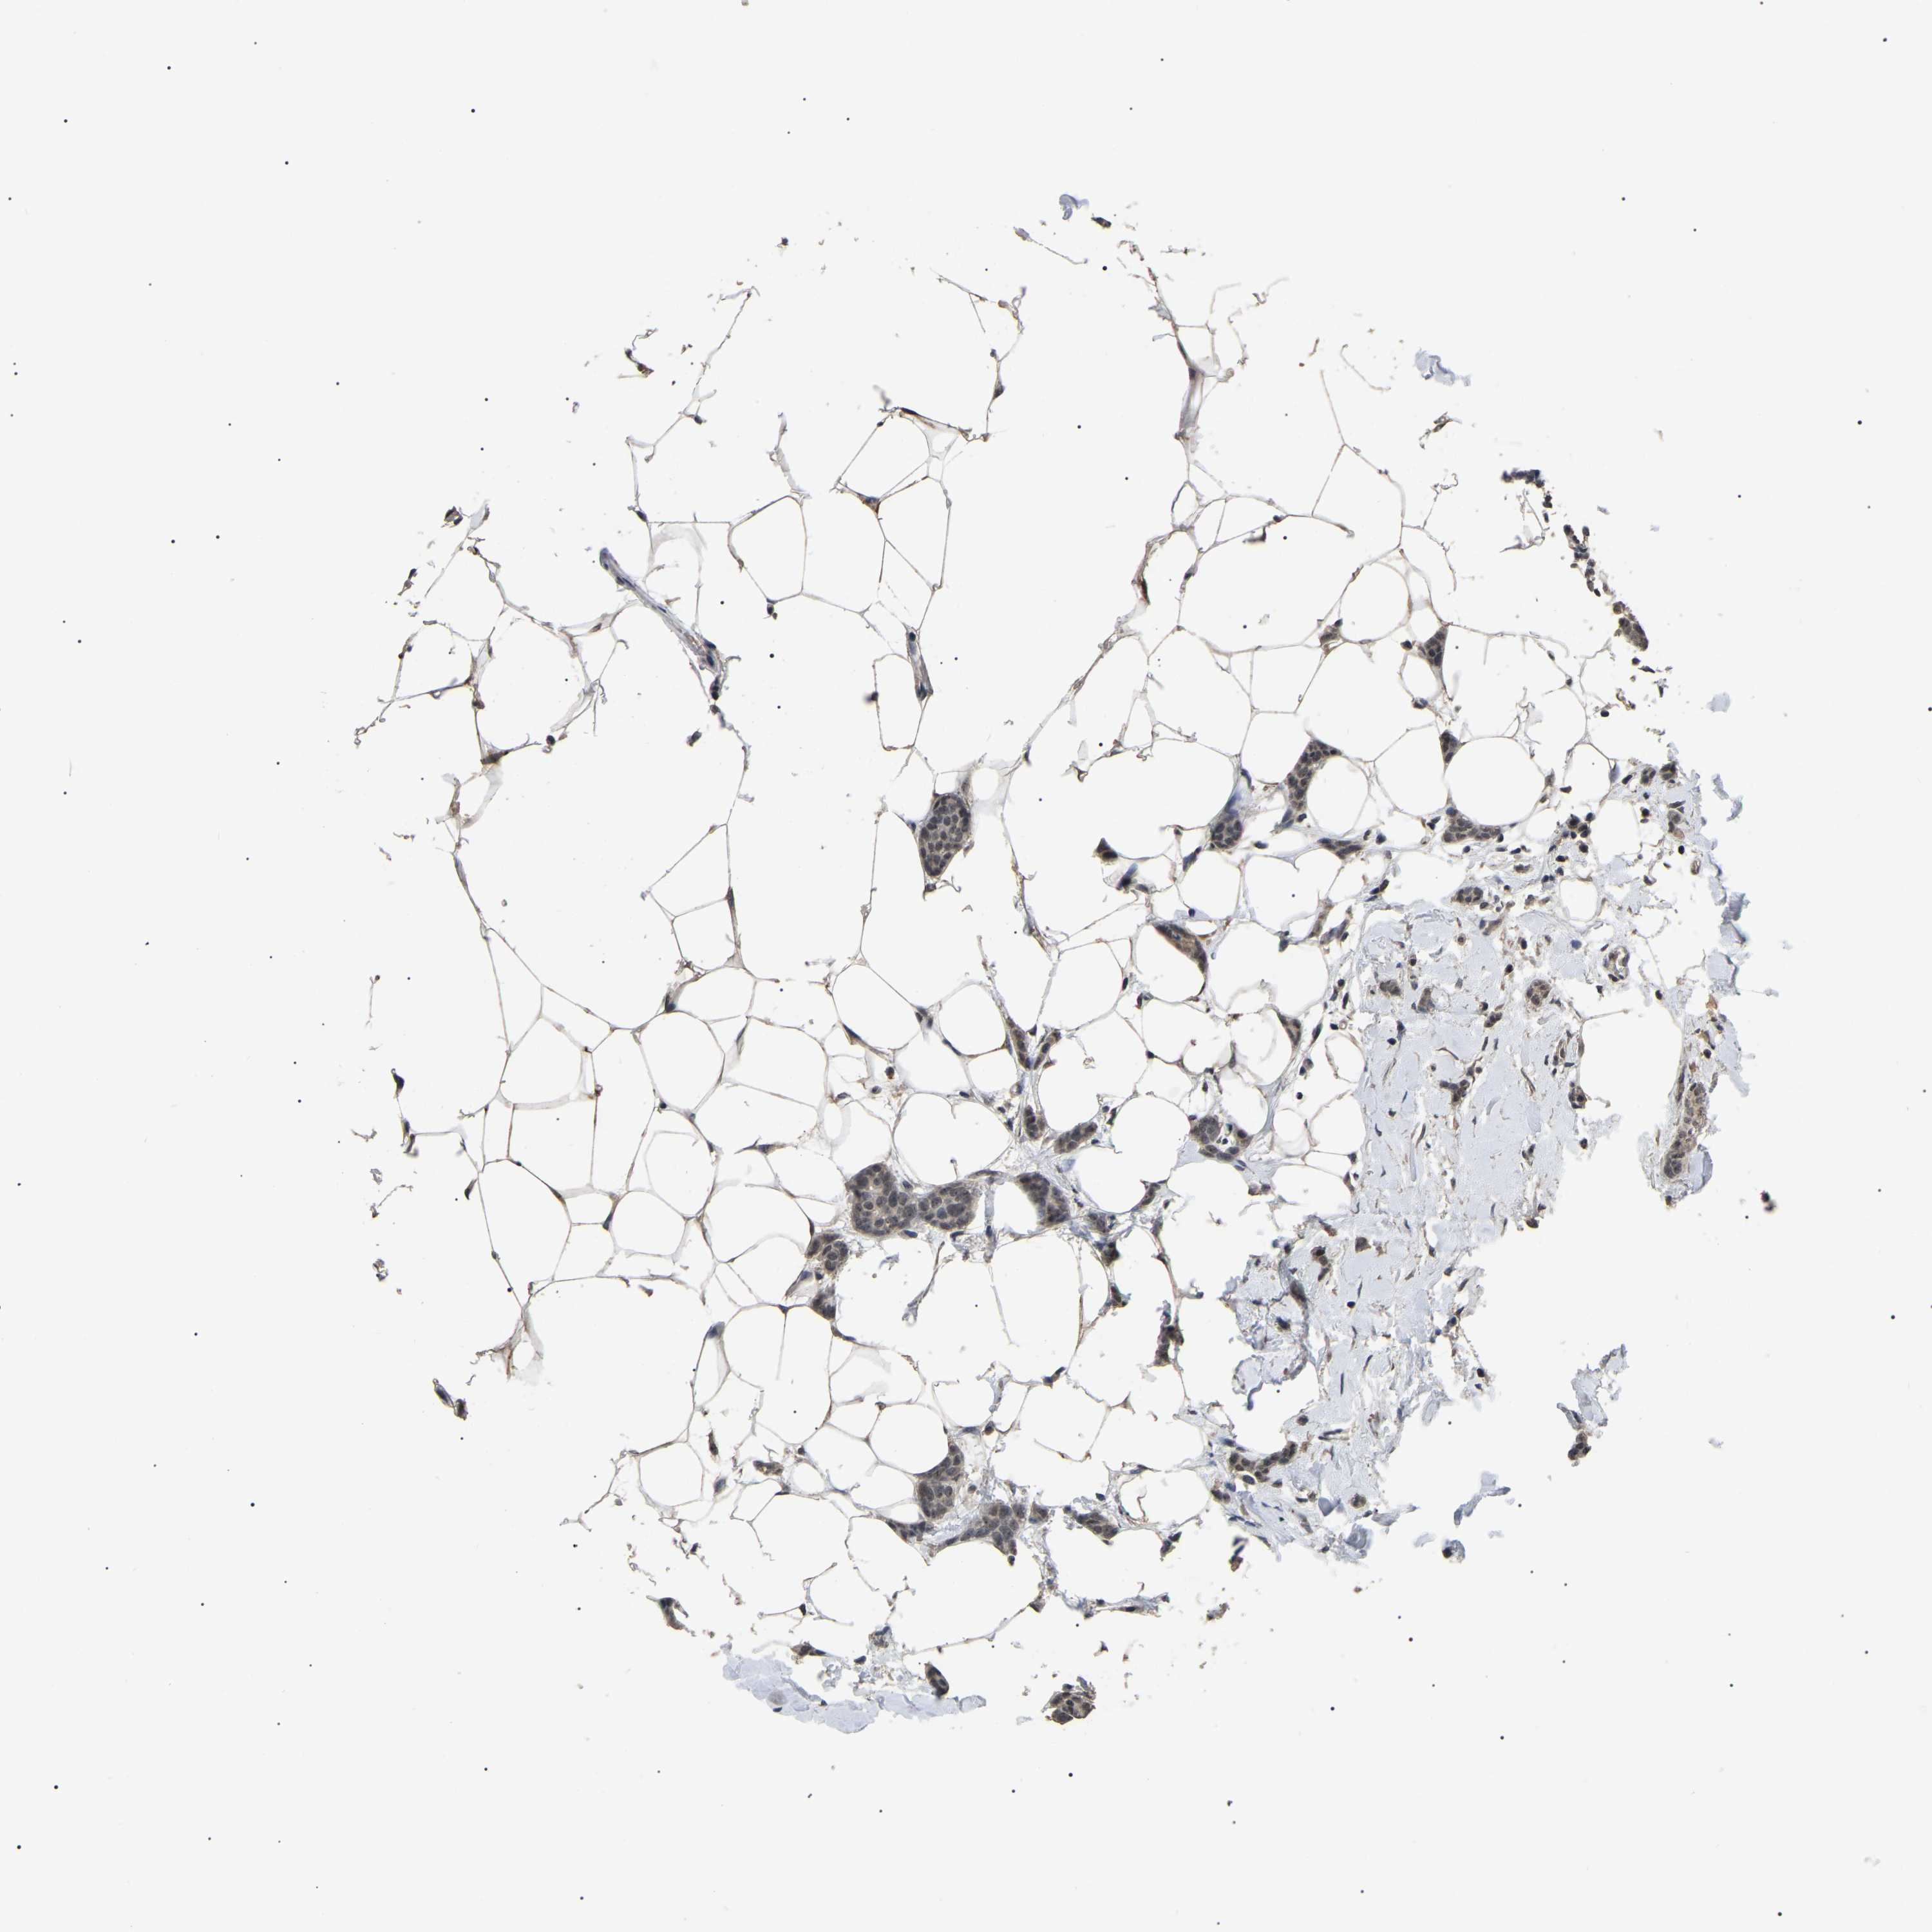

CANCER BREAST CANCER Show tissue menu

BRCA TCGA BRCA VALIDATION PROTEIN EXPRESSION